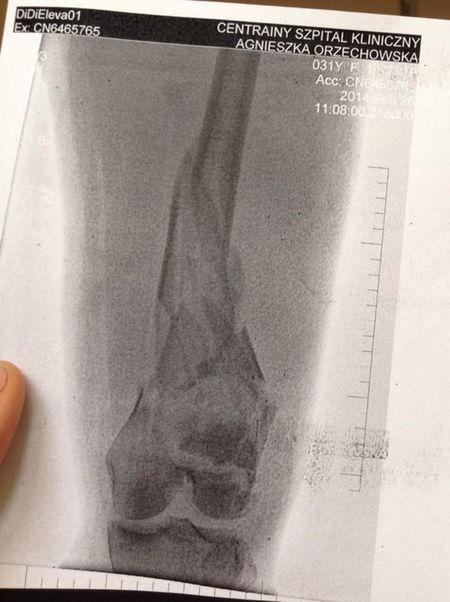

Orzechowska ma połamane obie nogi.

Otarłam się o śmierć. Mam gwóźdź w kolanie. Pierwszy raz byłam w śpiączce - napisała na swoim profilu na Facebooku.